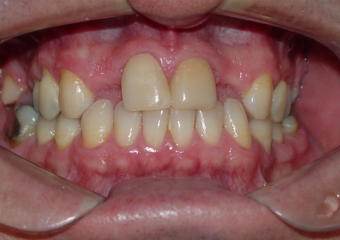

Imagens iniciais

Sorriso inicial